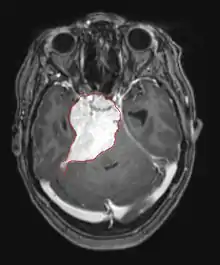

A tomografia computadorizada (TC) e a ressonância magnética (RM) podem detectar efetivamente uma neoplasia no cérebro. A RM é mais sensível que a TC para identificar lesões, mas contraindicações para pacientes com marcapasso cardíaco, próteses incompatíveis, clipes metálicos e outros. A TC continua sendo o método de escolha para detectar calcificações dentro de lesões ou erosões ósseas da calota craniana ou da base. A utilização de agentes de contraste, que são iodados no caso da TC e paramagnéticos ( gadolínio ) no caso da RM, permite a aquisição de informações sobre a vascularização e integridade da barreira hematoencefálica, uma melhor definição do tumor tumoral comparado ao edema circundante e à geração de hipóteses sobre o grau de malignidade . O exame radiológico também permite avaliar os efeitos mecânicos e consequentes alterações nas estruturas cerebrais decorrentes do tumor, como hidrocefalia e hérnias, cujos efeitos podem ser fatais. Finalmente, na preparação para a cirurgia, esse diagnóstico pode ser usado para determinar a localização da lesão ou a infiltração do tumor em áreas vitais do cérebro. Para isso, a RM é mais eficiente que a TC, pois pode fornecer imagens tridimensionais.

As ferramentas de diagnóstico por imagem radiológica destacam a mudança no tecido neoplásico em comparação com o parênquima cerebral normal (através de alterações na densidade do tecido fotografado eletronicamente na TC e na intensidade do sinal na RM). Como a maioria dos tecidos patológicos, os tumores também são reconhecidos por um acúmulo aumentado de água intracelular. Na tomografia computadorizada aparecem hipodensa, ou seja, de menor densidade que o parênquima cerebral, na tomografia de ressonância magnética nuclear com relaxamento spin-lattice T 1 hipointenso e em relaxamento spin-spin T 2 bem como a ponderação de prótons (PD) hiperintensa.

A área saudável do cérebro não deve mostrar nenhuma luminescência específica em uma imagem radiológica. Portanto, nem é preciso dizer que é dada atenção a faixas de sinal de contraste maiores.

No tecido tumoral, em geral, a maior proporção de realce pelo contraste se deve à barreira hemato-tumor particular que permite a passagem de iodo (TC) e gadolínio (RM) para o espaço intersticial extravascular intratumoral. Isso aumenta o sinal (densidade ou intensidade) do tumor. No entanto, deve-se ter cuidado para garantir que o realce do contraste não diferencie definitivamente a neoplasia do edema periferida. De fato, o achado anátomo-patológico no tecido tumoral de glioma infiltrante maligno, como no glioblastoma e no astrocitoma anaplásico, também mostra além do edema vasogênico causado pela destruição da barreira hematoencefálica pelo tumor. Esta última condição clínica é pouco detectável pelo diagnóstico por imagem.

A tomografia computadorizada do cérebro normalmente mostra uma massa de tecido que pode ser realçada por qualquer contraste. Na TC, os gliomas de baixo grau geralmente parecem isodensos ao parênquima normal e, portanto, podem não apresentar realce pelo contraste. Da mesma forma, lesões na fossa posterior do crânio são difíceis de identificar na TC. Consequentemente, os resultados dessa tomografia isoladamente nem sempre são suficientes para fins diagnósticos. Em casos duvidosos, o uso da ressonância magnética mais sensível é essencial.

Na ressonância magnética, um tumor intracraniano aparece como uma lesão maciça que pode se tornar mais luminescente após o uso do agente de contraste. No entanto, há sempre uma anomalia de sinal na ressonância magnética, que indica a presença de neoplasia ou edema vasogênico. Normalmente, o aumento da luminescência (realce pelo contraste) é indicativo de um tumor de grau mais alto de malignidade. Um anel contrastante é característico do glioblastoma, com a porção luminescente correspondendo à parte vital do tumor maligno e a área mais escura-hipointense à necrose tecidual.